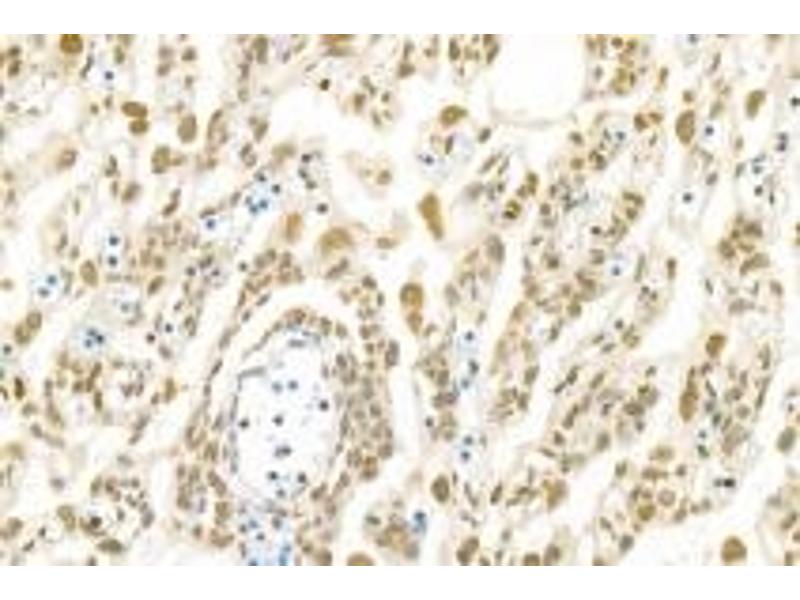

- IHC/IF (H,M,R) 1:600-1:1200/1:400-1:800

- PNN, also named as DRS or 140 kDa nuclear and cell adhesion-related phosphoprotein, is a 717 amino acid protein, which belongs to the pinin family. PNN localizes in the plasma membrane and is expressed in placenta, lung, liver, kidney, pancreas, spleen, thymus, prostate, testis, ovary, small intestine, colon, heart, epidermis, esophagus, brain and smooth and skeletal muscle. PNN is expressed strongly in melanoma metastasis lesions and advanced primary tumors. PNN as a transcriptional activator binds to the E-box 1 core sequence of the E-cadherin promoter gene. PNN is involved in the establishment and maintenance of epithelia cell-cell adhesion. PNN is a potential tumor suppressor for renal cell carcinoma.